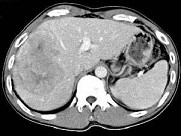

- 单项选择题根据所提供的图像,最可能的诊断是 ( )

A、肝血管瘤

B、FNH

C、肝癌

D、肝腺瘤

E、以上都不是